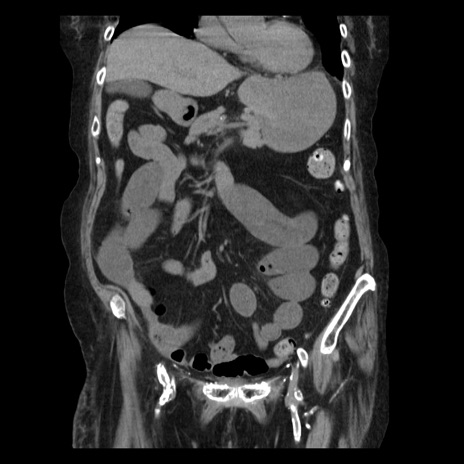

症例14(冠状断像)

【症例】 90歳代女性

【主訴】 腹痛・嘔吐

【現病歴】今朝から左側腹部痛を認めた。 経過観察していたが、嘔吐を認めたため来院。

【既往歴】 子宮癌術後

【身体所見】 意識清明、BP 127/54mmHg、P 98bpm Sp02 95%(RA)、BT 35.8°C、腹部平坦・軟腸ぜん動音聴取良好、右下腹部圧痛(+) 反跳痛なし

【データ】WBC 9800、CRP 0.46